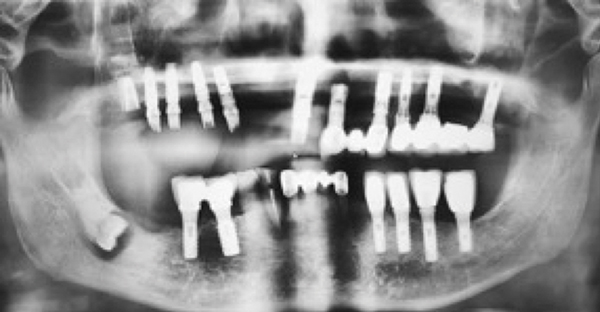

General Emergency Cosmetic Dentistry Ortho. Another major concern for dental implants along the upper row of teeth is the impact these implants can have on sinuses. Upper jaw dental implants can protrude into the sinus cavities causing swelling of the sinuses.

Because the roots of upper teeth can extend up into the floor of the sinus dental implants which are designed to act as tooth roots can push into the sinus and allow bacteria to. However there are surgeons that will explain that a perforated sinus will heal on its own and not to be concerned. More often then not one to two millimetres of an implant can penetrate the sinus cavity during placement of the implant without any untoward effects or long term compications.

Patients who do not have a sinus lift or bone graft before getting their dental implants have an increased risk of developing sinusitis after surgery particularly if the implant pokes through the jaw into the sinus cavity. Some surgeons would say that the surgery was sloppy. When receiving a graft the bone may come from your own hip or tibia autogenous bone a cadaver allogeneic bone or from cow bone.

After surgery sinus lift complications symptoms may include pain swelling infection the loss of the sinus lift graft fixture migration sinusitis and more. Call Marielaina Perrone DDS at 702-458-2929. In some cases dental implants can be placed simultaneously as the sinus lift.